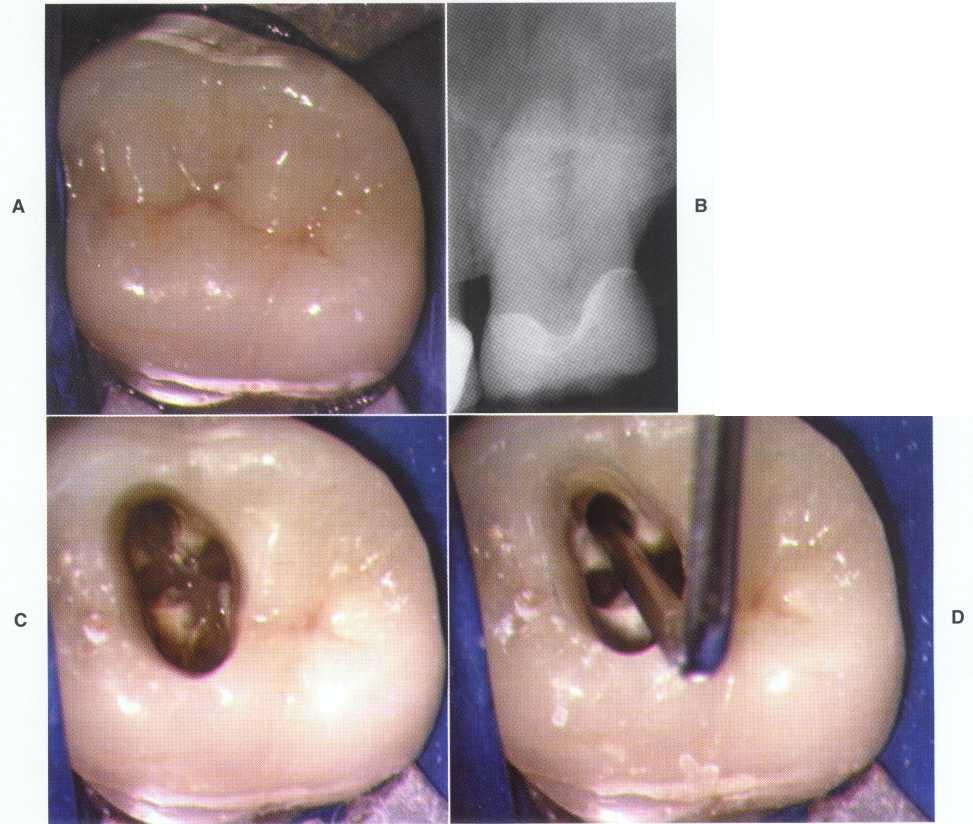

FIGURE 1-1

A 32-year-old woman presents for treatment of spontaneous pain that keeps her awake at night. She relates a history of orthodontics and a frenectomy as an adolescent, as well as traumatic injury to the maxillary anterior area during a basketball game. Clinical examination reveals normal-appearing soft tissues, scar formation consistent with location of the suture placed after the frenectomy, and discoloration of the maxillary left central incisor, tooth #9.